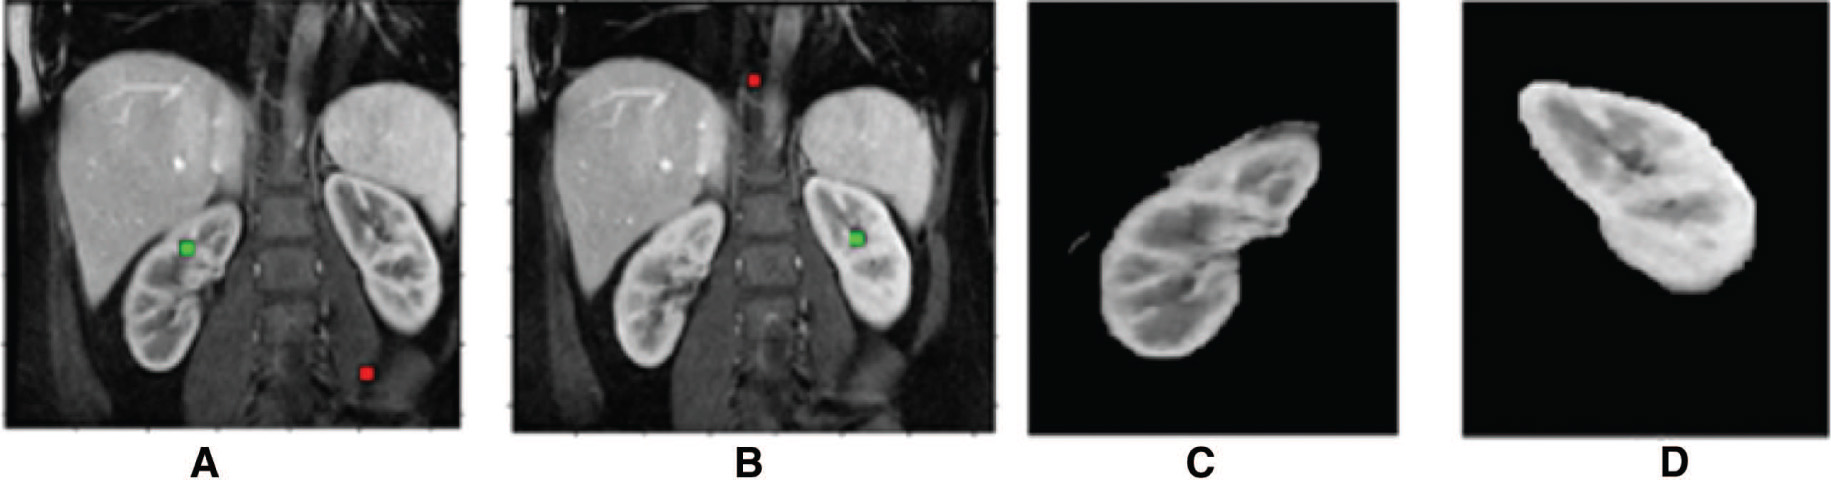

The parameters of the FCM algorithm are cluster fuzziness value (f = 2), a number of clusters (c = 3), and stopping criterion (ε = 0.001). Cost function minimization takes place by comparing the changes in membership function or the cluster center at two consecutive iterations. Cost function minimization takes place when the change in consecutive values of the fuzzy membership function is less than the stopping criterion (ε = 0.001). The parameters of the Fuzzy local information C-means (FLICM) algorithm are number of clusters (cnum = 4), weighting fuzzy exponent membership (m = 2), window size (w = 3), maximum iteration (imax = 500), and threshold value (th = 0.001). In the FLICM algorithm, the fuzzy factor has to be determined in each iteration and the computational complexity is high. The FCM and FLICM segmentation results are depicted in Figure 6. The Lankton algorithm evolves the initial contour based on the local neighborhood statistics and can segment the image into two homogeneous regions [42], and the results are depicted in Figure 7. In graph cut algorithm, the objective is to extract the object from the background by performing an optimum cut, and the results are depicted in Figure 8. Table 1 depicts the segmentation algorithms ranking for the characteristics spatial information, region continuity noise immunity, selection of parameters, the complexity of algorithms, computation time, and accuracy.

Graph Cut Algorithm for Anatomical Organ Delineation; (A, B) Input Images with Seed Point Selection, (C, D) Graph Cut Segmentation Result.

The DC values corresponding to the results in Figure 7 are 0.92, 0.90, 0.94, and 0.95. For graph cut segmentation, the DC values corresponding to the results in Figure 8 are 0.94 and 0.93. The following inferences are also made from the review of segmentation models: the noise immunity can be improved by the proper choice of filtering approach based on medical imaging modality, parameter selection is vital in segmentation, and optimization algorithm can be employed for improving the results. The computation complexity can be relaxed by using graphical processing unit (GPU) utilizing parallel processing. This work emphasizes the need for hybrid segmentation model for improving the accuracy and incorporation of optimization technique for tuning of parameters.